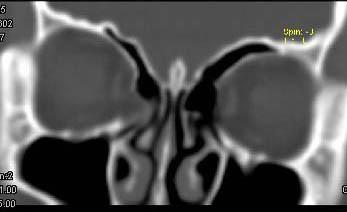

问题 女,25岁,因眼部外伤来院就诊,CT如图所示,最可能诊断是 ( )

选项 A、右眼眶内外侧壁骨折伴筛窦积血 B、蝶骨骨折伴筛窦积血 C、右眼眶内侧壁骨折伴筛窦积血 D、右眼眶外侧壁骨折伴筛窦积血 E、右侧颧弓骨折伴筛窦积血

答案 A